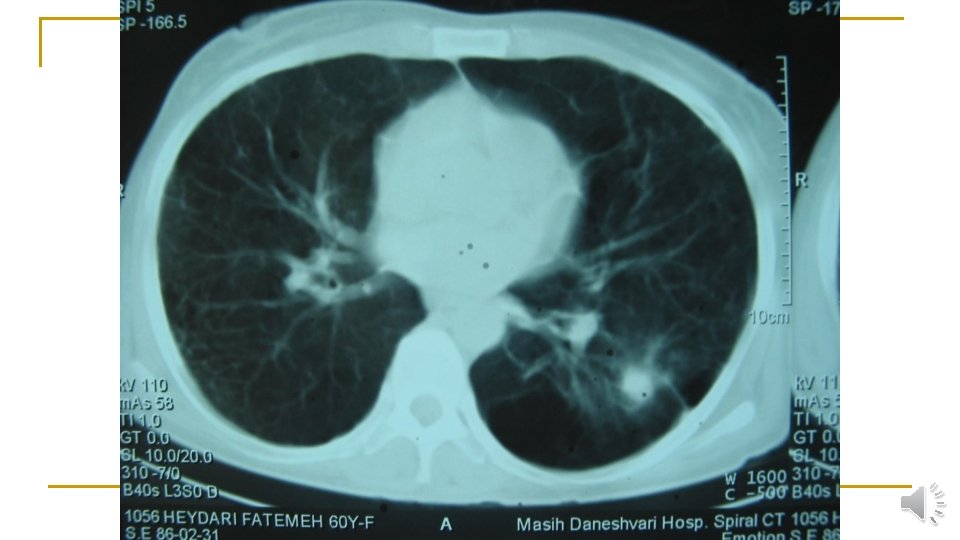

Lung CT scan